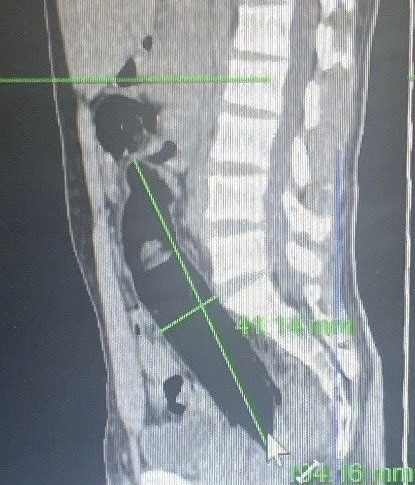

Bệnh viện đã tiến hành chiếu chụp cắt lớp vi tính đánh giá vị trí dị vật và nội soi đại trực tràng để gắp dị vật. Qua phim chụp, bác sĩ cũng hoảng vì dị vât quá lớn chèn vào đường tiêu hóa.